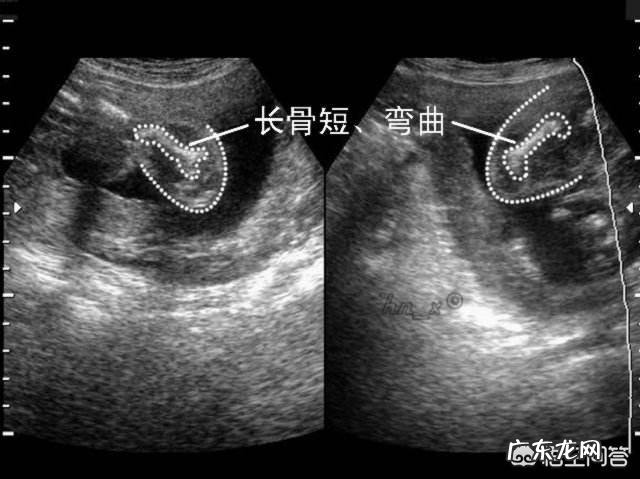

平时一定注意按时产检 , 关注胎儿的生长发育情况 。如果缺氧 , 胎儿会生长发育迟缓 。如果双顶径、股骨长、腹围这些指标都很正常 , 说明胎儿的发育没有受到妈妈睡眠姿势的影响 , 妈妈可以继续坚持自己的做法 。